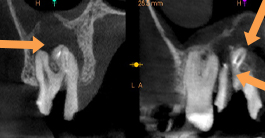

左下小臼歯の動揺を主訴に来院。根管内容物と最近感染組織を除去し、根管内を消毒し吸収した骨が回復となった。

歯根周囲に骨透過像が認められる。細菌感染により骨が吸収が疑われる。骨吸収により動揺が認められた。

歯根周囲に骨透過像が認められる。細菌感染により骨が吸収が疑われる。骨吸収により動揺が認められた。

根管治療後。歯根周囲に骨の回復を認める。歯の動揺も無くなり、被せ物をして、問題無く機能している。

根管治療後。歯根周囲に骨の回復を認める。歯の動揺も無くなり、被せ物をして、問題無く機能している。